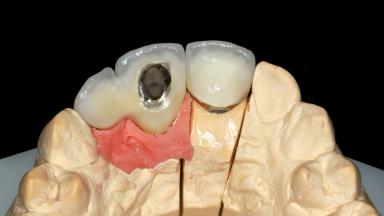

Replacement of an Upper Right Central and Lateral Incisor with an Implant-Supported Crown and a Distal Cantilever

This 20-year-old woman was referred to our department in July 2006. Four months earlier, she had experienced dental trauma to the anterior maxilla when traveling in South America. The emergency treatment included emergency root canal treatment of teeth 12 and 11. Tooth 21 was also subjected to endodontic treatment later. At the initial examination, the patient was not in pain but reported increased mobility of tooth 12. The clinical examination revealed a high smile line, medium thickness of the soft tissue, and rectangular tooth forms. Discoloration of tooth 12 was evident. The periapical radiograph provided by the referring dentist indicated a fracture line at both teeth 12 and 11. A cone-beam computed tomography (CBCT) scan confirmed these fractures. No pathology was found to be associated with tooth 21.

| Abutment Type | Customized |

| Prosthesis Type | FDP |